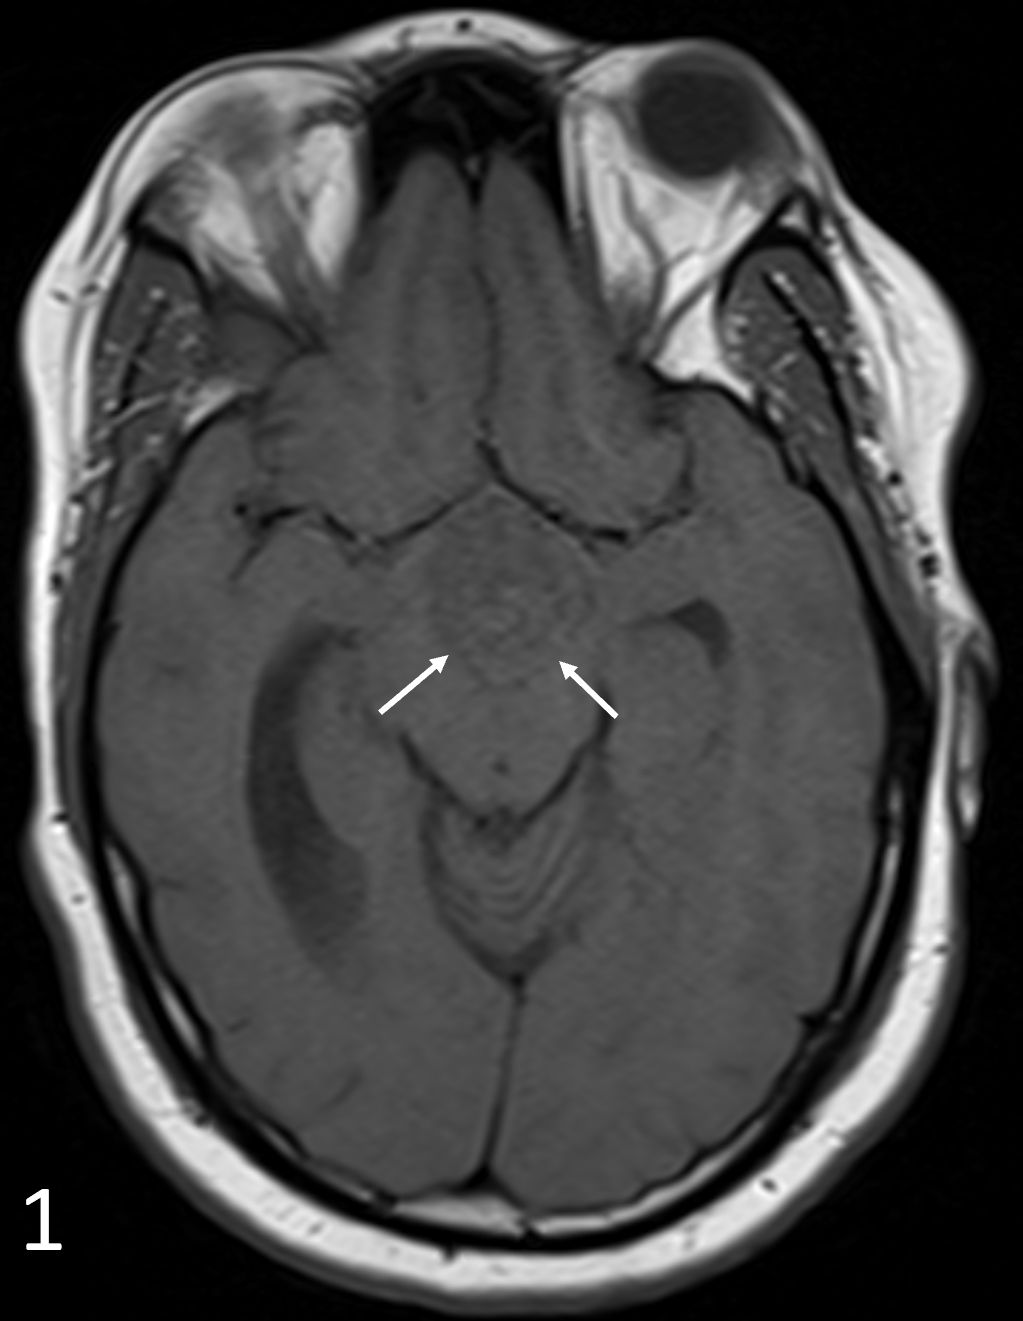

A 36-year-old man was referred to a psychiatry practice for a years-long history of migraines that had been unresponsive to treatment with numerous medications. The patient had sustained a significant TBI...